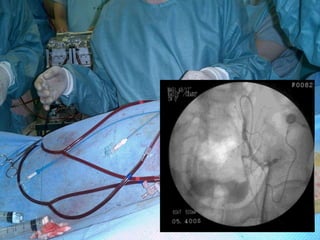

После катетеризации и ангиографии a. cystica

проведены курсы регионарной ПХТ (N = 6-36, медиана 18)

Cysplatini 0,05 mg/m²

Adriablastini 0,02 mg/m²

С сентября 1997 г. по декабрь 1999 г., после планового обследования, катетеризации и ангиографии

мочепузырных артерий, выполнен курс регионарной ПХТ (цисплатин, 50 мг/м² и адриабластин, 20

мг/м²) в объеме 36 сеансов. К концу 1999 г. отмечена полная ремиссия опухоли.

Август 2001 г. - выполнена ангиография сосудов мочевого пузыря. С октября 2001 г. по февраль

2002 г. проведено VI курсов регионарной ПХТ. По результатам КТ органов малого таза (2002) -

полная ремиссия опухоли, подтвержденная результатами ТУРМП-биопсии.